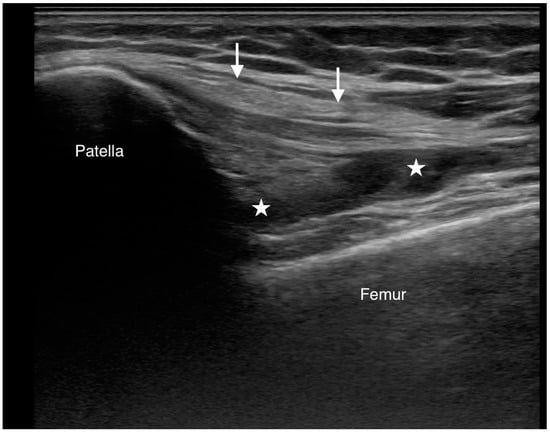

Figure 4.

The extruded cement and capsular laceration appeared to contribute to significant knee effusion, as observed on ultrasound. A longitudinal ultrasound scan of the anterior knee demonstrates effusion in the suprapatellar pouch (star). The quadriceps tendon is indicated by a white arrow.